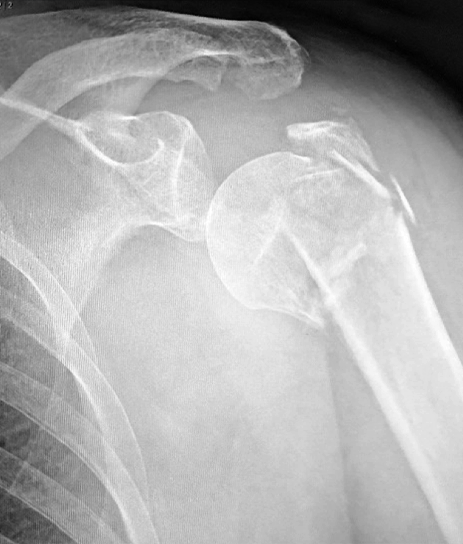

For fracture and revision treatment

The system offers a set of modular Proximal Bodies in several sizes and heights to be paired with a broad range of Modular Stems, available in different diameters and lengths as well as different surface and coating options for cemented and cementless fixation.

The Proximal Bodies’ spiked surface, together with m-l and a-p holes for suture fixation, allow for stable and physiologic tuberosities reattachment. The modular concept of the fracture components supports the surgeon in achieving adequate joint restoration even in cases with poor anatomical landmarks.1